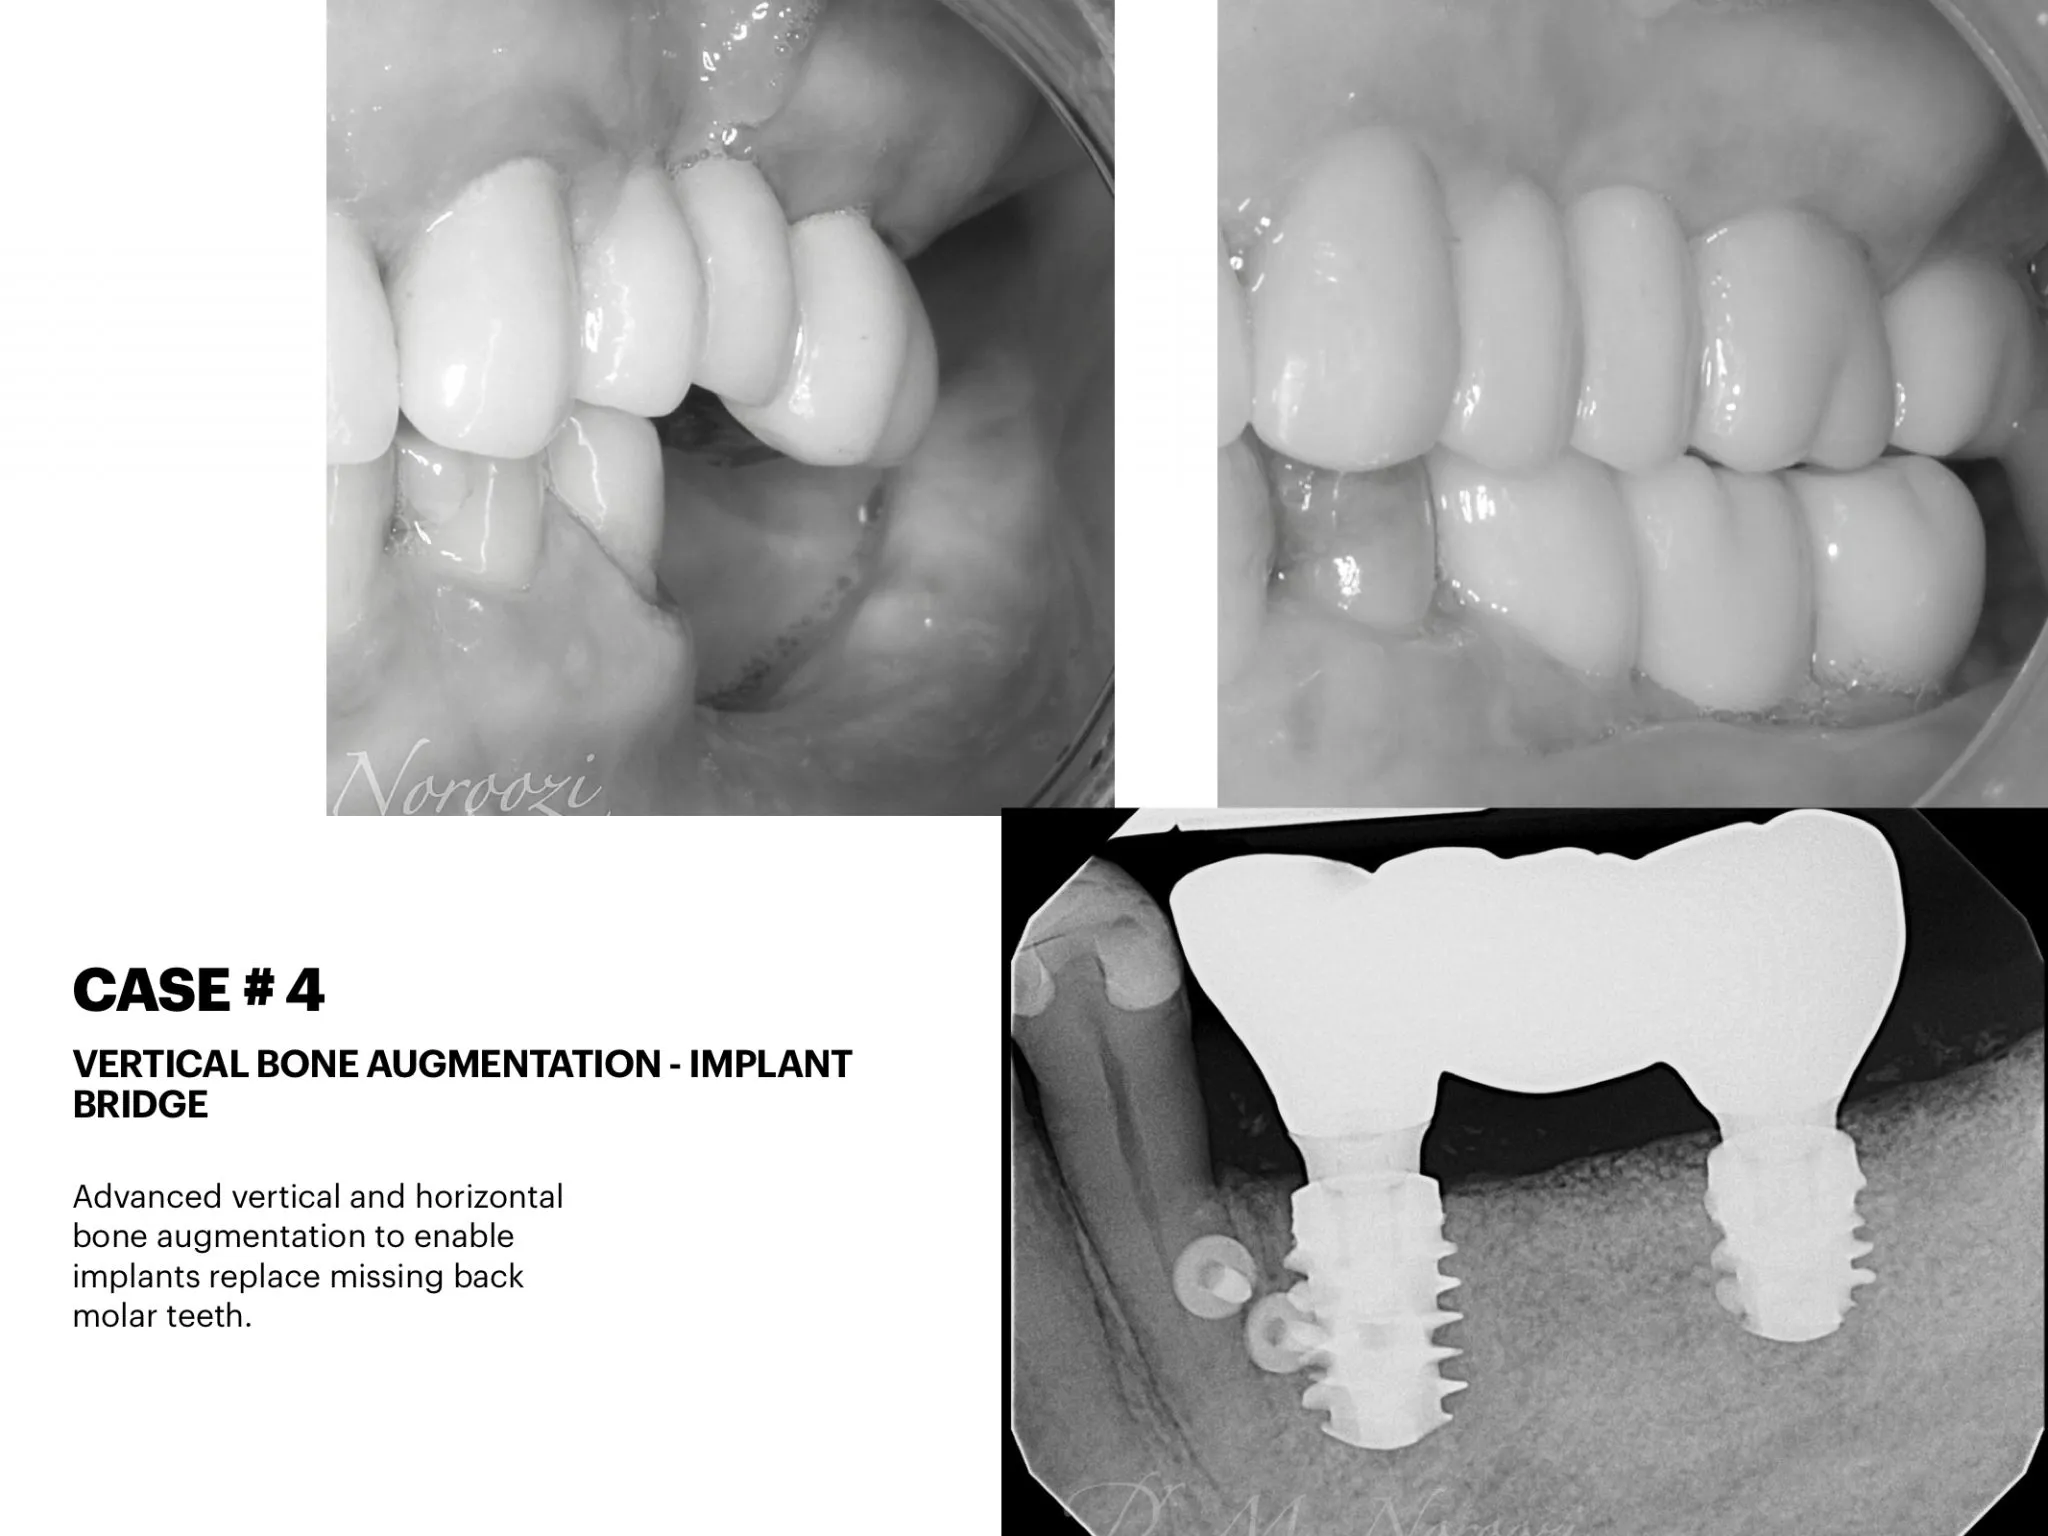

Vertical Bone & Gum Augmentation & Guided Implant Placement